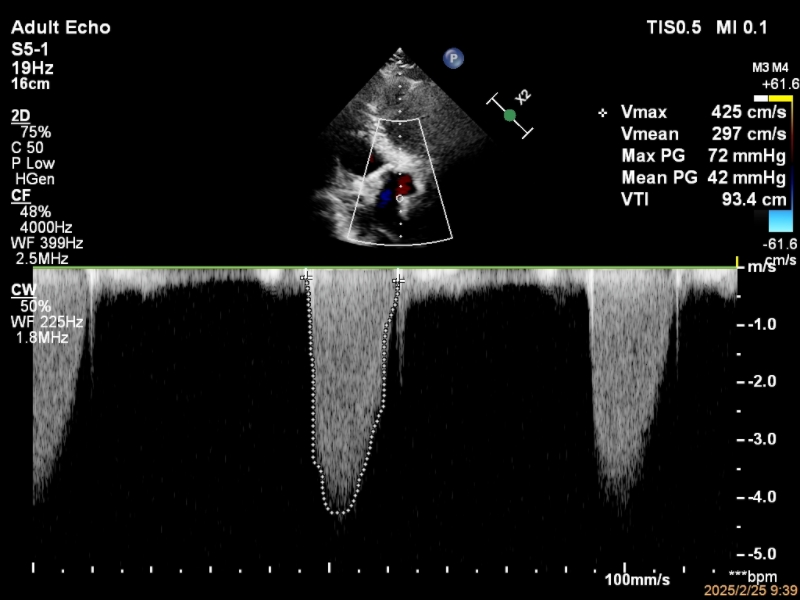

患者郑先生一年来胸闷不适,近日到北京安贞医院南充医院就诊。经心脏彩超检查,医生发现其主动脉瓣重度狭窄【主动脉瓣上流速(Vmax):425cm/s,Max PG:72mmHg,mean PG:42mmHg】、主动脉瓣二瓣化畸形(图1)。考虑到郑先生年轻且无手术禁忌症,手术治疗成为必然选择。

图1